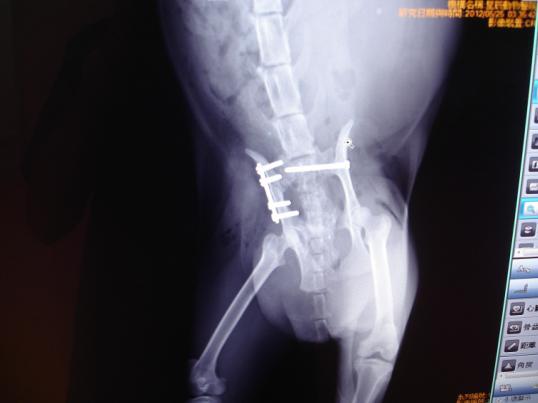

主題: 三重車禍骨盆骨折移位癱瘓復健貓-第2次申請醫療費用 申請者姓名: 敏大哥 花色: 申請日期: 2012-08-15 16:02:48 申請者部落格: 申請者臉書網址: 所在縣市/合作醫院: 台北市/星辰動物醫院 治療費用: 36010元 需求人數: 39人 已結案 (2013-06-27 13:29:16) 報名人員: 陳明蘭(已付款)、Latte(已付款)、Joy(已付款)、大雨(已付款)、大雨(已付款)、zatti(已付款)、Huan Feng Tz(已付款)、Ginny Cat(已付款)、Choco Chen(已付款)、Choco Chen(已付款)、E(已付款)、永顗(已付款)、KO.PON(已付款)、Orak Yeh(已付款)、Vicky Wu(已付款)、Lydia(已付款)、F.y. Yang(已付款)、M.K(已付款)、謝佩芳(已付款)、CANDY(已付款)、陳玉君(已付款)、陳玉君(已付款)、Jessica I-Chin Pan(已付款)、Angie Chao(已付款)、Nikki、Nikki、戴小戴(已付款)、戴小戴(已付款)、Maru Pang(已付款)、Joanna Tang(已付款)、陳曉玫(已付款)、Shirley Chen(已付款)、Water(已付款)、五雞(已付款)、楊小馥(已付款)、蔡摳摳(已付款)、Mandy Wang(已付款)、Reinette(已付款)、Reinette(已付款)、大喵、Meow Purr Purr、Emily Chou x2(已付款)、 候補人員: Tracey Kao、邱冬梅、Faith Lin、Hoya、小舟、 動物病情說明: 三重網友李先生通報發現路倒貓, 求援"請支持流浪貓TNR計劃協會", 由我救援送醫至星辰動物醫院. 吳醫師研判疑似車禍造成癱瘓,拍X光確診這隻母貓已懷有身孕了! 腹腔胎兒約2週. 右側骨盆骨折. 左側腸薦關節移位. 需要開刀打骨板和骨釘接合.

5/22入院後先點滴輸液調養身體. 於5/25進行3個手術-(1)左側腸薦關節移位,手術復位植入骨螺絲釘. (2)右側骨盆骨折,手術植入骨板並縫合完成. (3)骨折將子宮體切斷,胚胎受損, 導致體內大出血. 手術取出子宮卵巢胚胎. 因為重症外科手術費用較高, 所以於6/1先針對外科手術醫療費35,000元募款. 醫助編號:374. 醫助內容請參考網址: